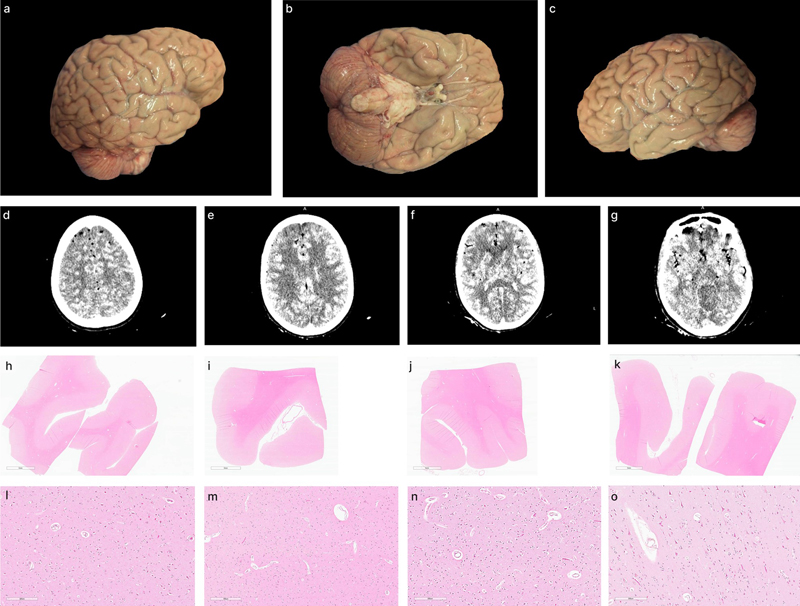

Quality of perfusion based on histology

The quality of perfusion on histology was graded based on the clearance of intravascular material from blood vessels, with each vessel as not cleared, partially cleared, or fully cleared (Figure 8). The extent of clearance across all blood vessels in the WSI was then graded on a 0–3 scale to estimate the perfusion quality of that tissue sample (Figure 9). These grades were found to have an ICC of 0.804 (95 % CI 0.675–0.885), indicating excellent interrater reliability. As a control, we also performed histology on the brain of one donor (#166) that was exclusively preserved via immersion fixation, which yielded grades of 0 in six brain regions and grades of 1 in the remaining six brain regions. For additional comparison, we graded the vessel clearance in a larger set (n = 36) of exclusively immersion-fixed brain frontal cortex from a previously described cohort (Garrood et al., 2025). We found that vessel clearance was significantly higher in perfusion-fixed samples compared with immersion-fixed samples (mean perfusion-fixed sample grade = 1.59, mean immersion-fixed sample grade = 0.42, t-test, p-value = 1.56e-7). These results demonstrate that vessel clearance – and therefore our grading metric – is not entirely specific to perfusion, and that the partial clearance of intravascular material from blood vessels can also result from other mechanisms. However, vessel clearance is significantly greater in perfusion-fixed samples, consistent with the expected effect of perfusion in removing intravascular material.

Figure 8.

Representative histology images showing the degree of blood vessel clearance. This degree of clearance was determined across the entire WSI to determine the perfusion quality of each tissue sample. Donor IDs 147 (a, b), 78 (c, d), and 142 (e, f). Scale bars: 700 μm (a, c, e) and 200 μm (b, d, f). Scale bars: a, c, e: 700 μm; b, d, f: 200 μm.

Figure 9.

Representative histologic perfusion quality grades in WSIs. Grades were assigned on a 0–3 scale, where 0 indicates < 5 % clearance of intravascular material from vessels, 1 indicates 5–50 %, 2 indicates 50–95 %, and 3 indicates > 95 %. Grade 0: donor #166, left frontal cortex (a, b, c). Grade 1: donor #147, right occipital cortex (d, e, f). Grade 2: donor #107, right occipital cortex (g, h, i). Grade 3: donor #142, right occipital cortex (j, k, l). Scale bars: 200 μm (a, c, d, f, g, i, j, l), 8 mm (b), 7 mm (e, h), and 6 mm (k).

The mean perfusion quality grades based on histology, averaged across both hemispheres, were 1.91 ± 0.15 for the temporal white matter, 1.59 ± 0.16 for the frontal cortex, 1.41 ± 0.16 for the temporal cortex, 1.32 ± 0.15 for the thalamus, 1.27 ± 0.15 for the occipital cortex, and 0.45 ± 0.11 for the cerebellum (Figure 10). The cerebellum exhibited significantly lower perfusion quality than the other regions, including the thalamus and occipital cortex (t-test, p-values = 6.4e-5 and 0.0002, respectively). The occipital cortex, in turn, had significantly lower average grades than the temporal white matter, but not the frontal cortex (t-test, p-values = 0.0059 and 0.167, respectively). These data suggest that average perfusion quality with our approach is relatively lower in the cerebellum, a region supplied by the posterior circulation.